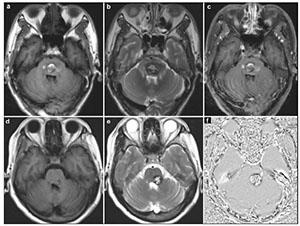

20170712151406 Figure 3 Case 1: Central pontine cavernous malformation. Axial gradient-echo image (a), enhanced T1-weighted postoperative with 72 hours (b) and enhanced T1- weighted postoperative scans at 3 month (c). White arrow showed the entry point.